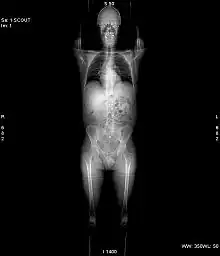

X-ray computed tomography operates by using an X-ray generator that rotates around the object; X-ray detectors are positioned on the opposite side of the circle from the X-ray source.

Structure

In conventional CT machines, an X-ray tube and detector are physically rotated behind a circular shroud (see the image above right). An alternative, short lived design, known as electron beam tomography (EBT), used electromagnetic deflection of an electron beam within a very large conical X-ray tube and a stationary array of detectors to achieve very high temporal resolution, for imaging of rapidly moving structures, for example the coronary arteries. Systems with a very large number of detector rows, such that the z-axis coverage is comparable to the xy-axis coverage are often termed cone beam CT, due to the shape of the X-ray beam (strictly, the beam is pyramidal in shape, rather than conical). Cone-beam CT is commonly found in medical fluoroscopy equipment; by rotating the fluoroscope around the patient, a geometry similar to CT can be obtained, and by treating the 2D X-ray detector in a manner similar to a CT detector with a massive number of rows, it is possible to reconstruct a 3D volume from a single rotation using suitable software.